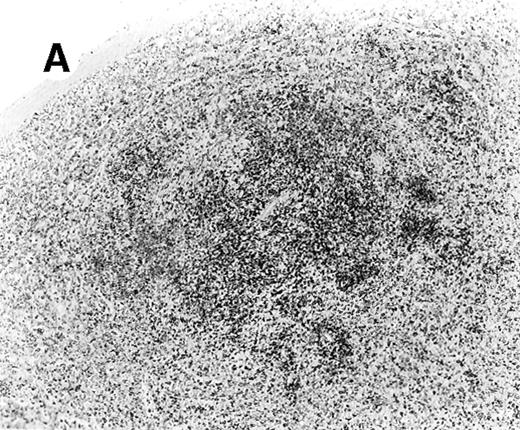

Staining for CD4 and CD8 in spleen from case 4.

(A) Low-power view of spleen shows that the lymphoid nodules are composed predominantly of CD4+ cells. (B) Relatively few CD8+ cells are seen. (C) The CD4+ cells are also EBER1+ (immunoperoxidase stained, hematoxylin counterstained, × 50).

ISH for EBV

In situ hybridization for EBV using the EBER1 probe showed striking positivity in the majority of the small lymphoid cells in all cases (Figure 4E). Correlation of the EBV positivity with the distribution of CD4/CD8 staining clearly indicated that the EBV-harboring cells were CD8+ in cases 2 and 5 (Figure 4E) and CD4+ in case 4 (Figure 5A-C). In addition, although an admixture of CD4+ and CD8+ cells had been previously noted in case 1, double staining for EBER1 and CD4 confirmed presence of EBV in the CD4+ population, with the CD8+ cells being clearly negative (Figure 6A,B). In the other 2 cases (cases 3 and 6), it was difficult to ascertain whether the CD4+ or CD8+ cells harbored the EBV, and double staining was not contributory.